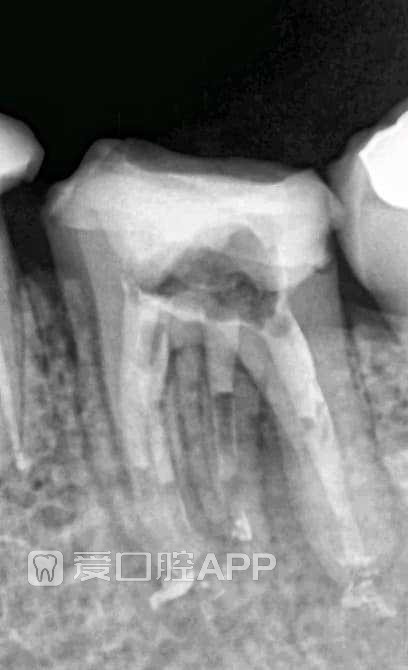

看个根管再治疗 by Mohamed Abdul-Aziz